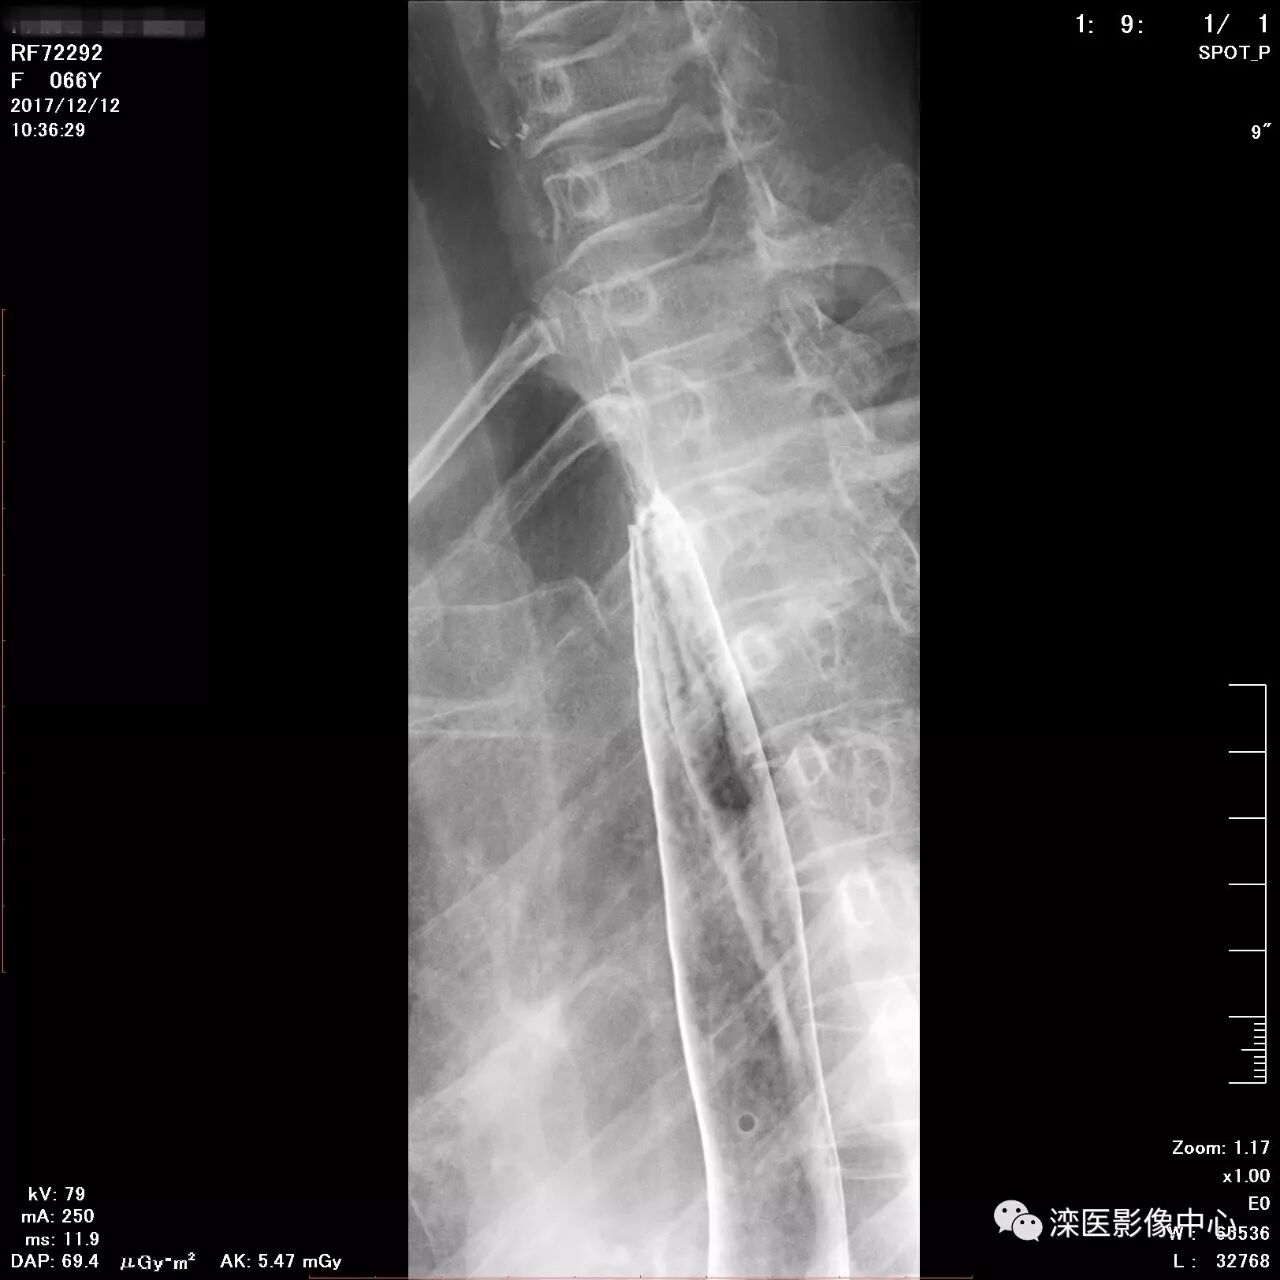

正位,显示食管、贲门及喉咽部的粘膜像)

(左前斜位,显示食管、贲门的粘膜像

(右前斜位,显示食管、贲门的粘膜像)

(以上图像是患者立位+卧位,通过变换体位,多角度显示了贲门胃底、胃体、胃大弯、胃小弯、胃窦、幽门及十二指肠球部、降部、水平部、升部的粘膜像和充盈像。本例患者女性,66岁,此次检查可以清晰显示胃小区结构,检查中发现患有慢性胃炎、胃下垂、十二指肠降部憩室)